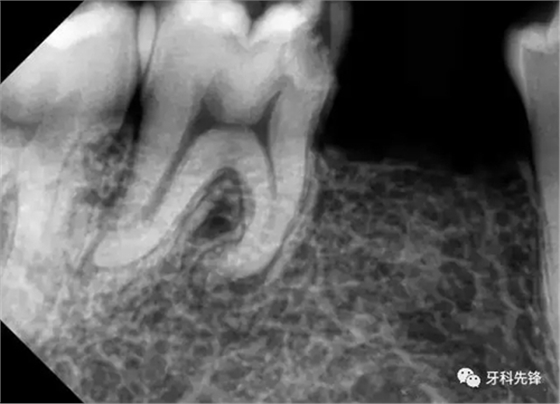

檢查: 男,23歲。46近中鄰咬合面齲洞,探痛(+),叩診叩痛(+),無(wú)病理性松動(dòng),X-ray示近中鄰咬合面暗影,近髓腔,牙根彎曲,根尖無(wú)明顯暗影,牙周膜增寬。

診斷:46急性牙髓炎

處置: 46右下牙槽神經(jīng)阻滯麻醉,46橡皮障隔濕,去凈腐質(zhì),開(kāi)髓,拔髓,GG鉆擴(kuò)大根管口,根管疏通,根測(cè),ML=19.5mm,MB=18mm,DB=DL=18mm,EDTA作用下M2鎳鈦機(jī)擴(kuò)至25#,試尖拍片,干燥根管,AHplus糊劑+牙塞尖+熱牙膠加壓根充,,聚羧酸鋅墊底,Z350納米樹(shù)脂充填,調(diào)合,拋光。